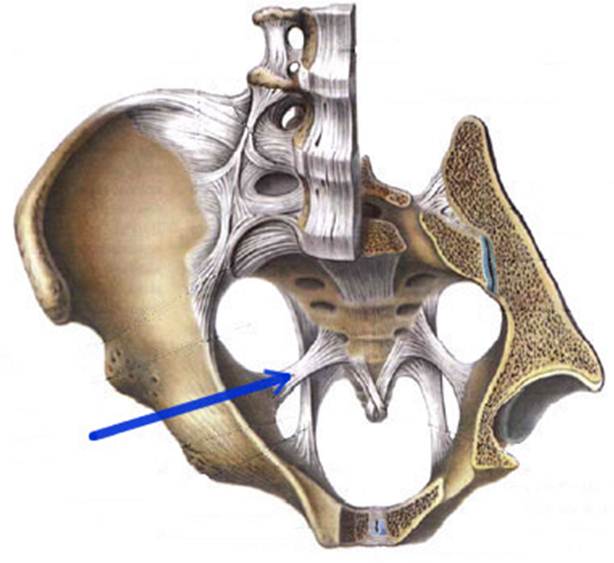

S: Стрелка указывает на lig. Sacrospinale

S: Стрелка указывает на лобковый симфиз (русский язык).

S: Стрелка указывает на foramen ishiadicum majus

S: Стрелка указывает на foramen ishiadicum minus

S: Стрелка указывает на membrana obturatoria (латинский язык).

S: Стрелки указывают на lig. iliofemorale

S: Стрелка указывает на lig. pubofemorale